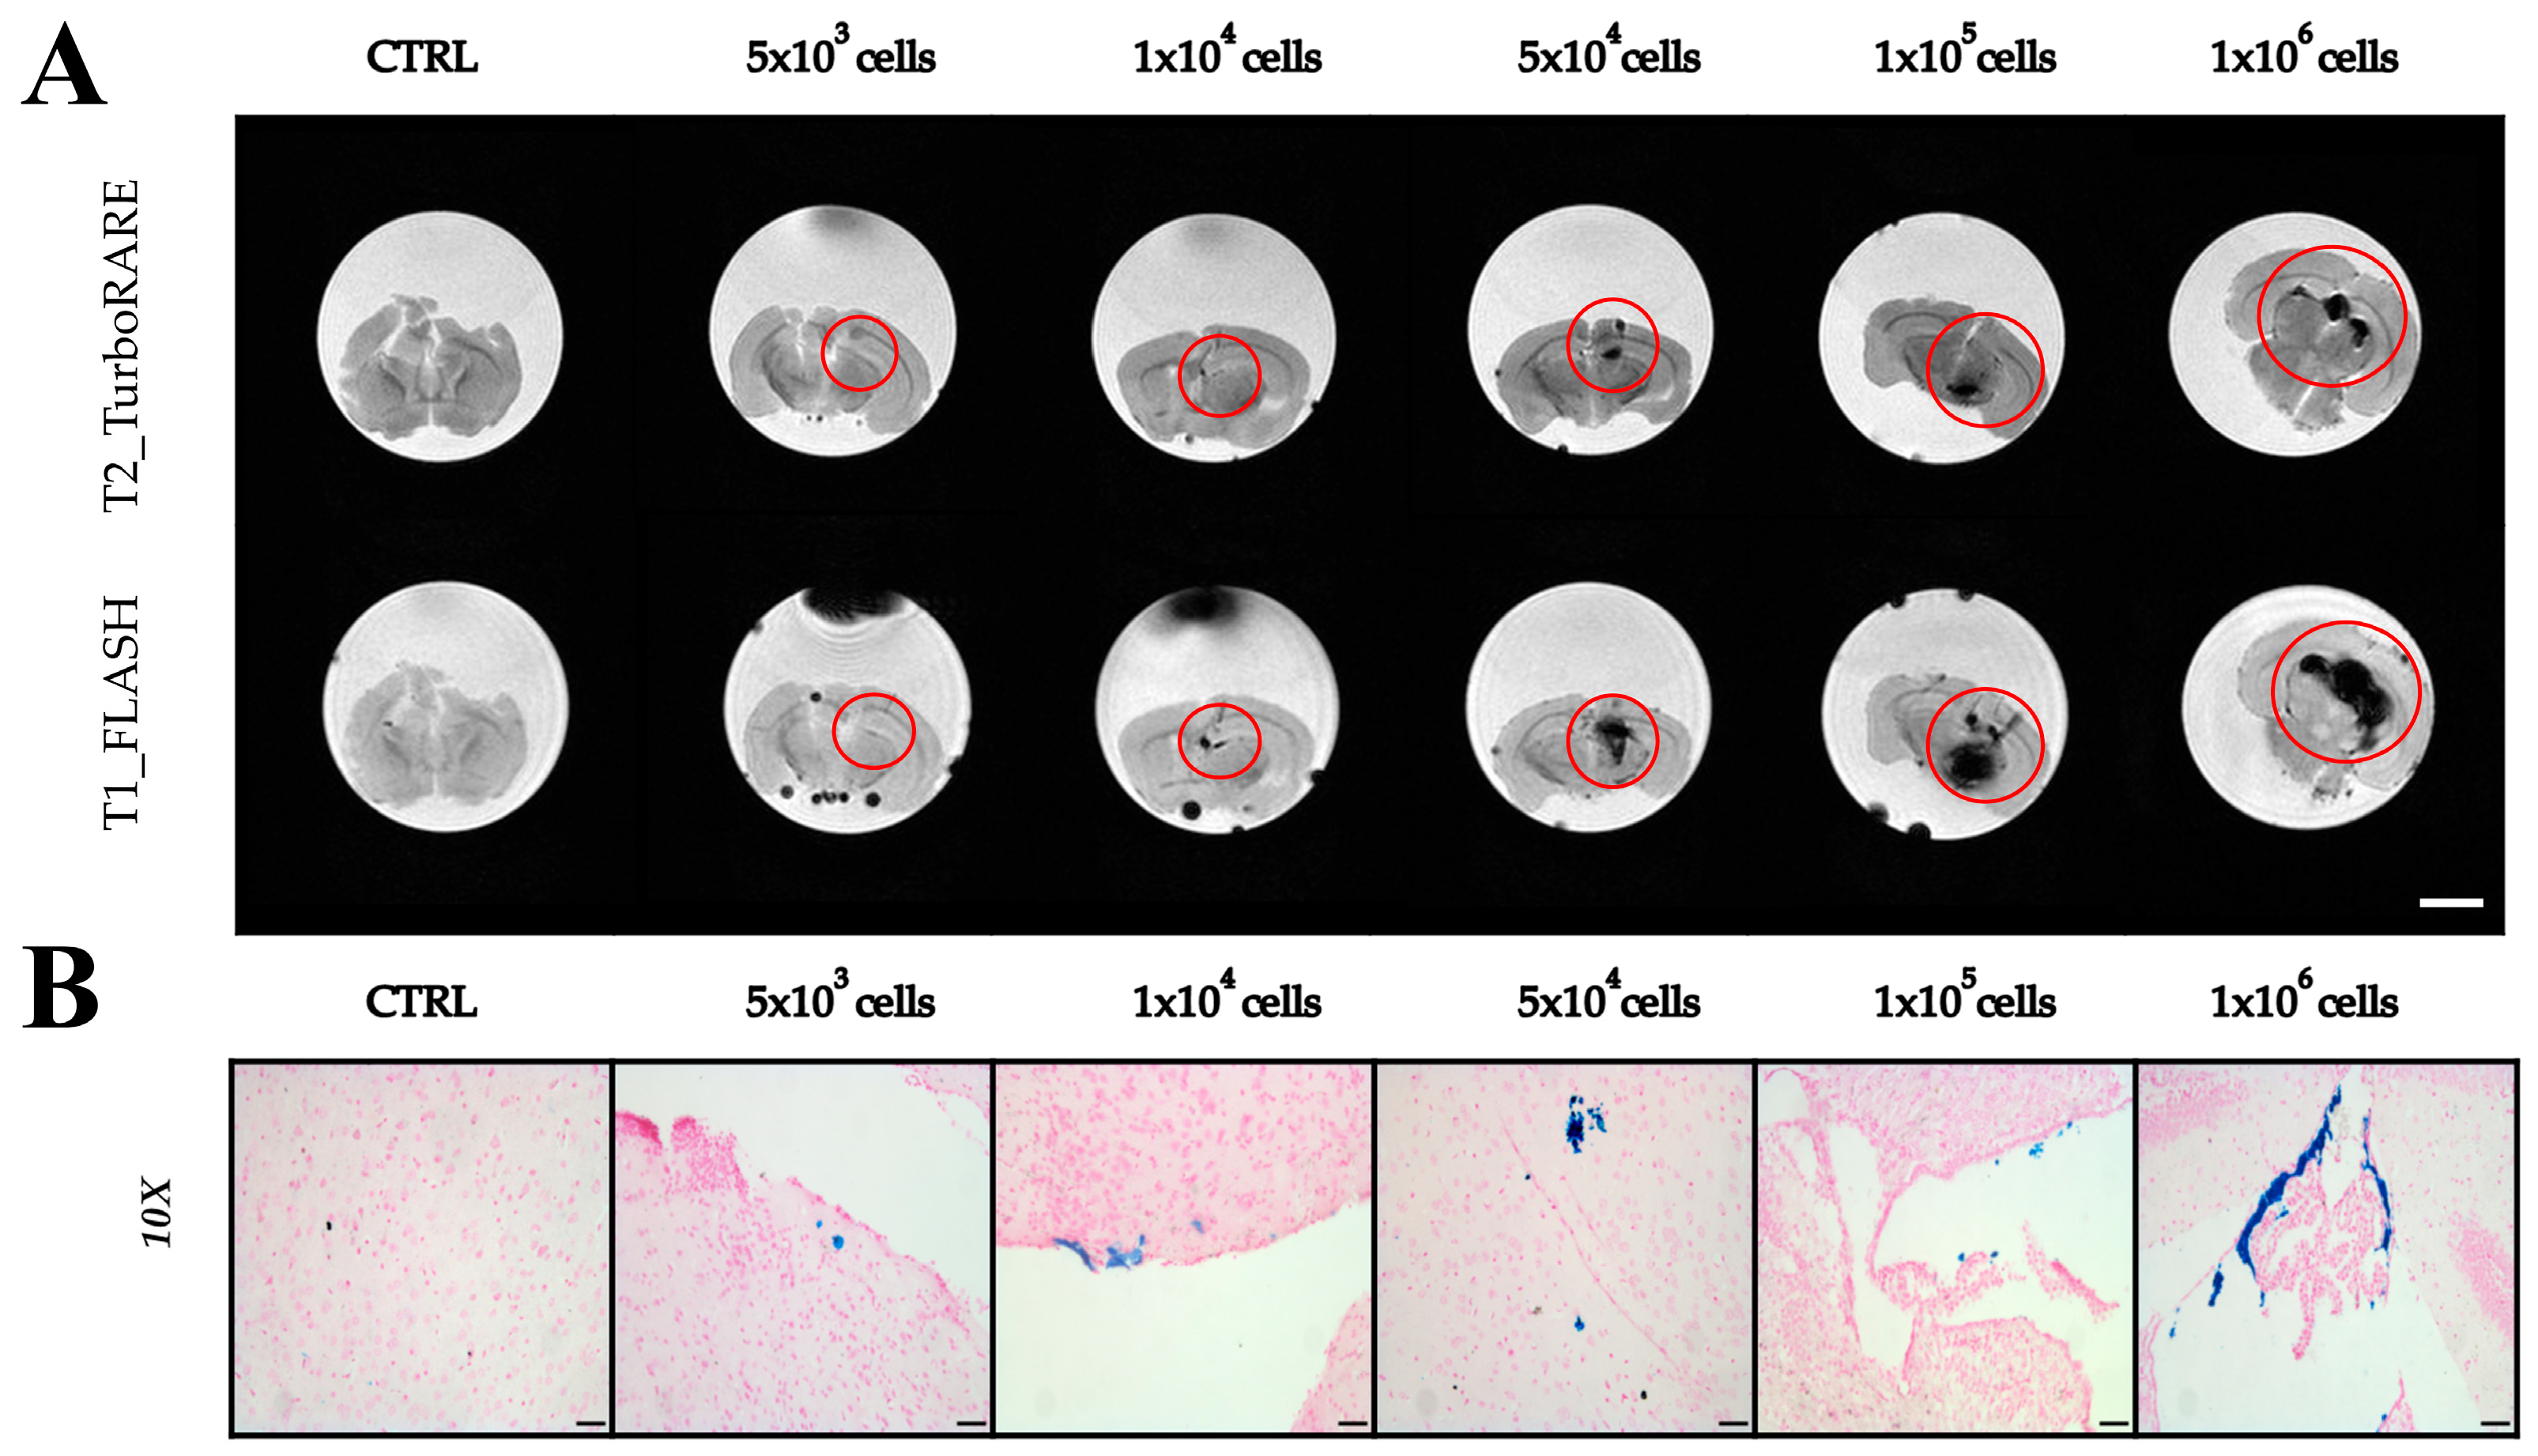

2.3. Imaging with Magnetic Resonance

2.4. Extraction of Extracellular Vesicles from ADAS-Labeled Cells